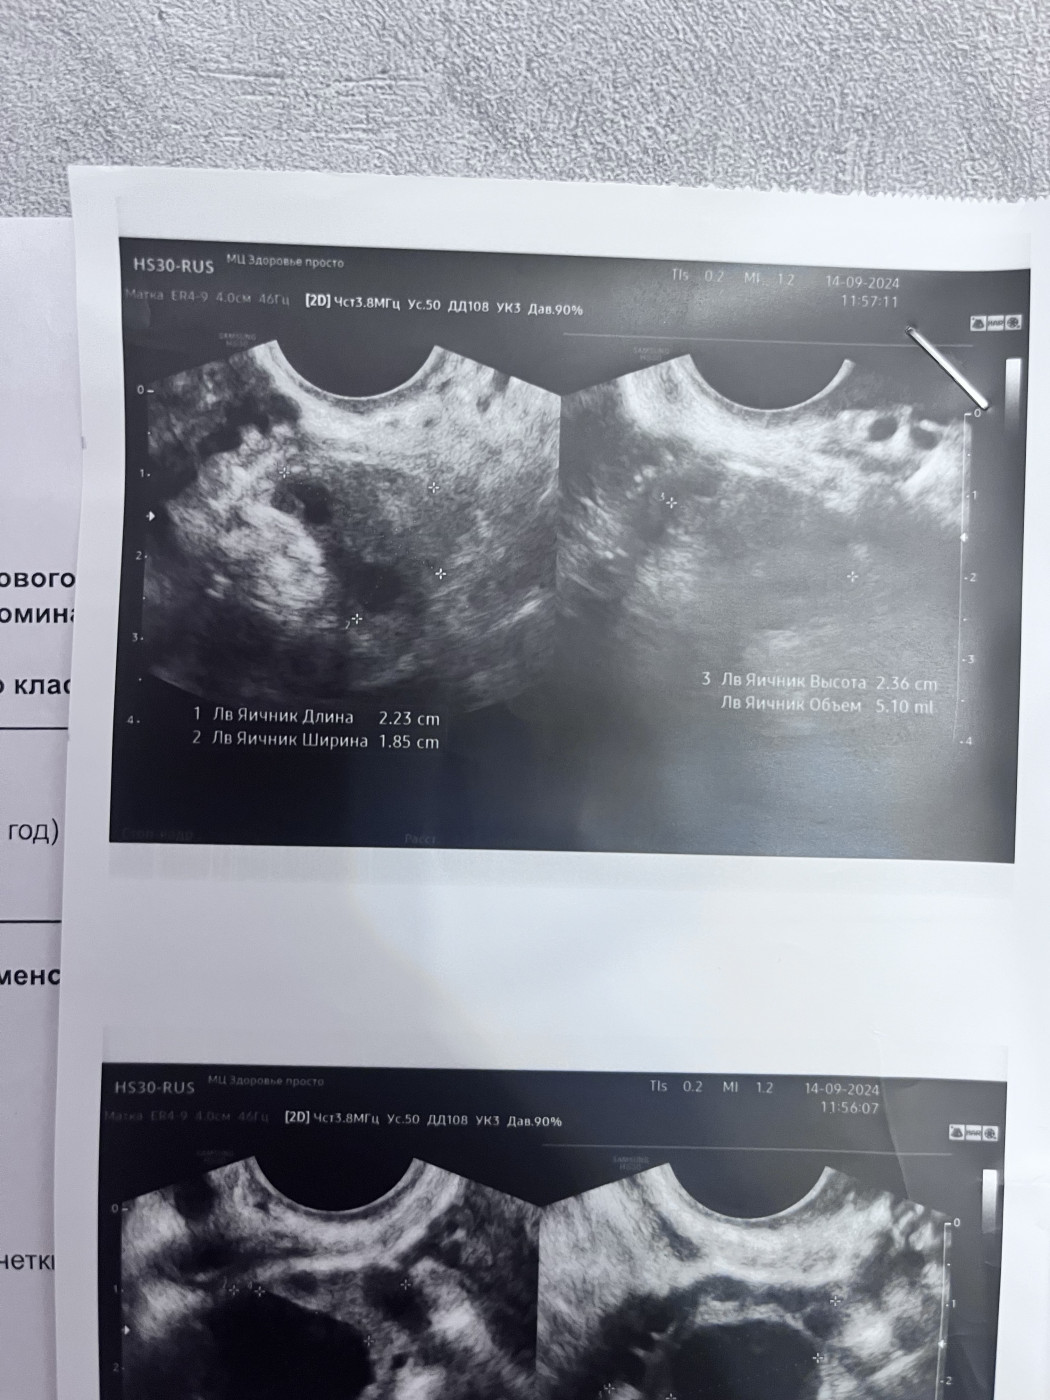

Поставили диагноз полип эндометрияНа 21 дне менструального цикла врач на узи увидела полип. Прикрепляю фото |

После менструального цикла назначили повторное узи, чтобы убедиться полип ли это. Также делала узи через месяц, 11 дней цикла. |